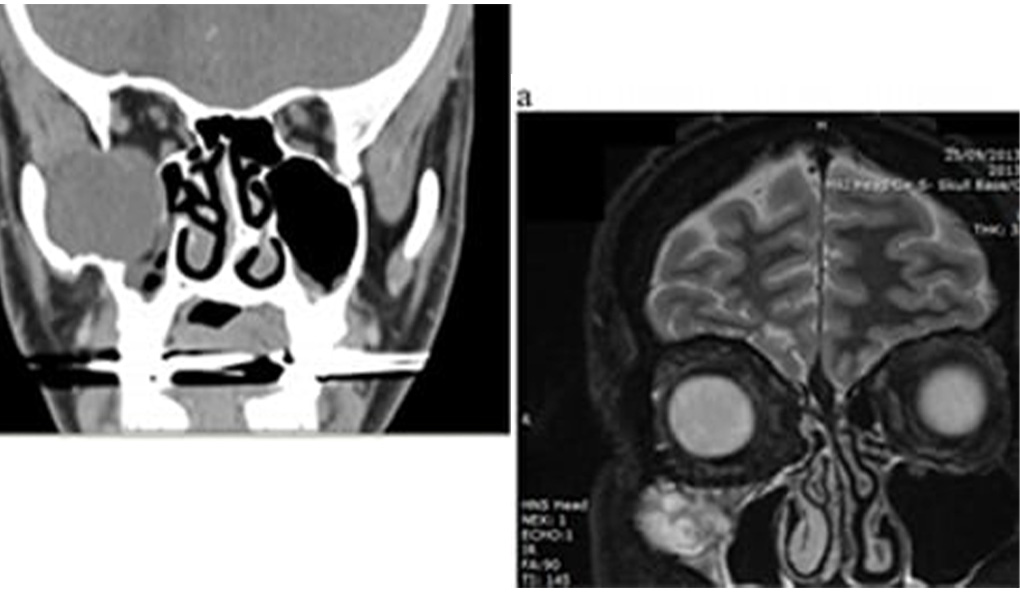

A 48-year-old man presented with an orbitomaxillary mass 31 years after repair of the orbital floor. He gave a history of progressive diplopia and paraesthesiae of the right infraorbital nerve. He also noted improvement in his long-standing post-traumatic enophthalmos. Imaging showed a large orbitomaxillary cystic mass, which was thought to be secondary to a silicone implant. The implant and the cystic mass were removed, and the orbital floor was reconstructed with titanium mesh. Histological examination confirmed an inclusion cyst. Maxillary antral lesions can present with symptoms such as sinusitis, paraesthesiae, diplopia, and orofacial pain, and they may arise from the lining of the sinus, or from surrounding structures such as the orbit, nose, or maxilla. This was a late complication of silicone elastomeric implants, and there are alternative treatments for defects of the orbital floor.